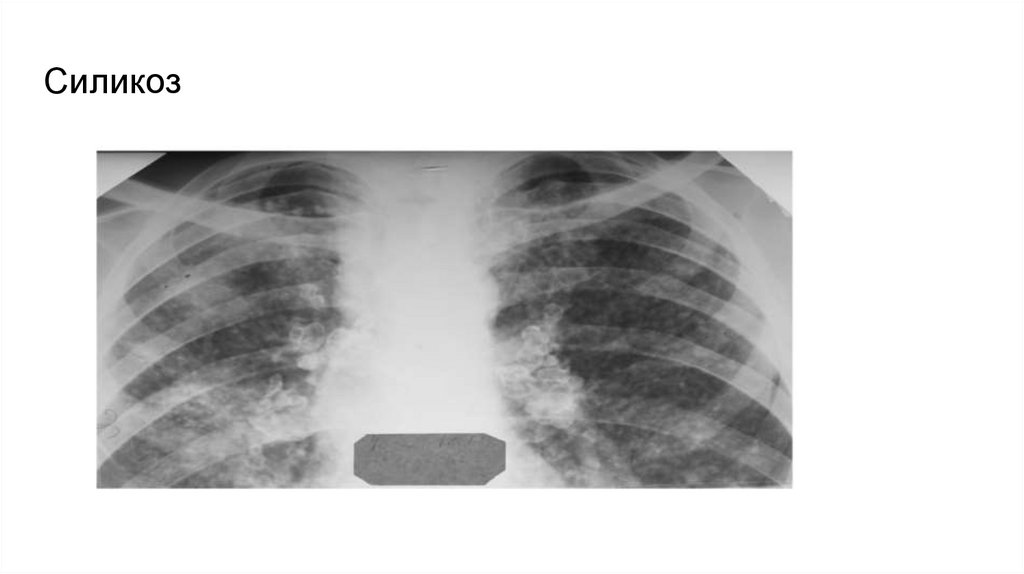

Category: medicinemedicine

20. СИЛИКОЗ

профессиональный анамнез; к пылеопасным профессиям относят-ся специальности в горнорудной отрасли (проходчики,

забойщики и др.), литейной промышленности (формовщики, пескоструйщики и др.) и фарфоро-фаянсового производства;

незаметное начало заболевания, длительное бессимптомное тече-ние, отставание клинической картины от

рентгенологических измене-ний в легких на годы

отсутствие симптомов интоксикации (нормальная температура тела) и нормальные показатели крови, а также отсутствие МБТ

в мокроте;

рентгенологически: локализация диссеминации и фиброзных изменений преимущественно в средненижних отделах легких;

более мономорфный (однотипный) характер узелков при силикозе, которые имеют примерно одинаковые мелкие и средние

размеры (до 5 мм), бо-лее высокую интенсивность и очерченность, чем очаги при туберкулезе; изменения в корнях легких по

типу «яичной скорлупы»